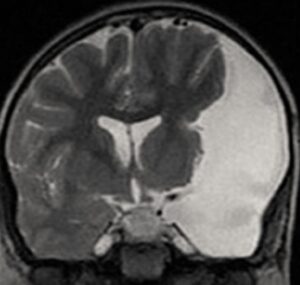

Os cistos aracnoides são bolsas cheias de líquido localizadas entre a membrana aracnoide e o cérebro ou a medula espinhal. Estes cistos são frequentemente descobertos incidentalmente, durante exames de imagem realizados por outros motivos. São os cistos intracranianos mais comumente encontrados na população geral.

A localização dos cistos pode influenciar sua relevância clínica. Eles são frequentemente localizados na fossa média, região suprasselar e cisterna quadrigêmea. Cistos maiores ou localizados em áreas críticas do cérebro podem ter maior potencial para causar problemas neurológicos, mesmo que se inicialmente assintomáticos.

O cisto aracnoide da fissura de Sylviana (SFAC) é o tipo mais comum de cisto aracnoide intracraniano, consistindo em 47 a 66% de todos os casos pediátricos. Os sintomas de apresentação do SFAC variam de aumento da pressão intracraniana a sintomas não específicos como atraso psicomotor, distúrbio comportamental e convulsões.

Por outro lado, os cistos aracnoides localizados próximos da linha média, como a aqueles localizados na região suprasselar, pineal ou da fossa posterior, podem causar sintomas de hidrocefalia obstrutiva ou efeitos de massa em estruturas neurais locais.